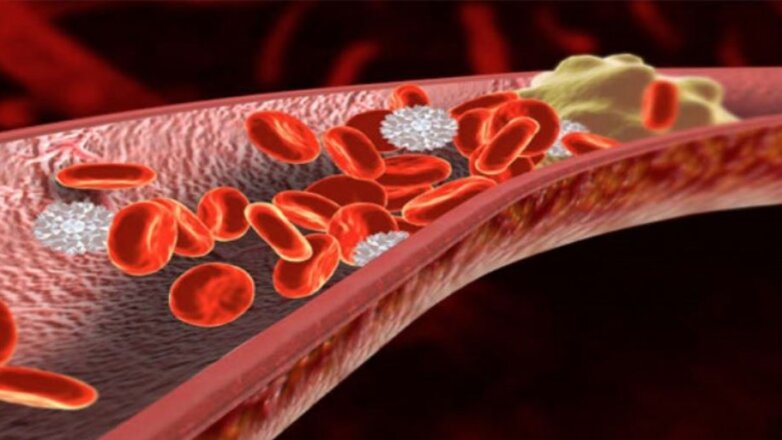

Κινήσου ενάντια στη θρόμβωση

Το μήνυμα «Κινήσου ενάντια στη θρόμβωση» ήταν το κεντρικό μήνυμα όλων των ομιλητών κατά τη διάρκεια Συνέντευξης Τύπου που οργάνωσε το Ι.Μ.Ε.Θ.Α., με αφορμή τον εορτασμό της Παγκόσμιας Ημέρας Θρόμβωσης (13 Οκτωβρίου). Ο εορτασμός της Παγκόσμιας Ημέρας Θρόμβωσης που φέτος κλείνει τα 10 χρόνια, έχει την επιστημονική αρωγή 19 Επιστημονικών Εταιρειών που σχετίζονται με τη […]